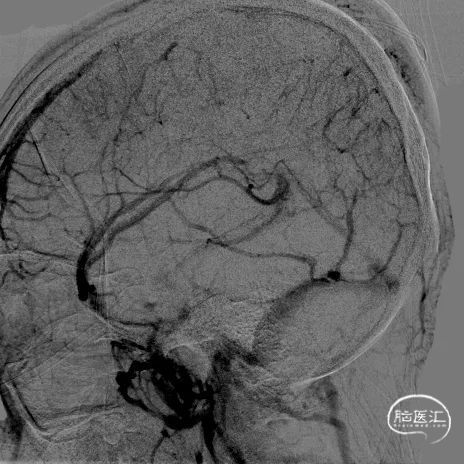

c) 大口径抽吸导管开通上矢状窦:

4A

4B

4C

4D

4E

4F

4G

4H

图注4:

4A 微导丝/微导管/ Penumbra ACE68 同轴技术向前推进至上矢状窦、引导ACE68进入上矢状窦远端

4B 侧位动态记录可以看到 ACE68良好的通过性

4C 微导管正位造影剂推注明确上矢状窦及窦汇区域也有大量栓子信号

4D 撤出微导丝及微导管, ACE68大口径抽吸窦汇区域,吸出大量血栓

4E 桡动脉造影提示上矢状窦仍有大量血栓,拟进一步推进ACE68 进行抽吸治疗

4F 微导丝微导管引导ACE68进入上矢状窦远端

4G-H 上矢状窦内ACE68反复抽吸后,造影可见上矢状窦恢复正常回流